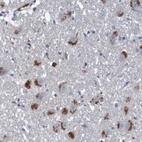

Immunohistochemical staining of human hippocampus shows strong cytoplasmic positivity in neuronal cells.